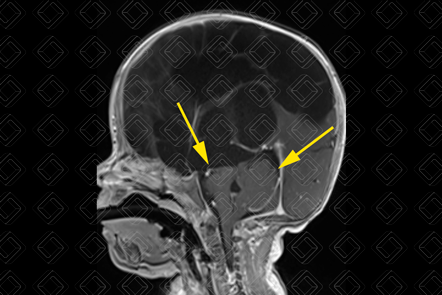

Texto alternativo para a imagem Figura 1. Créditos: Dra. Elazir Mota - Rio de Janeiro/RJ

Descrição das figuras 1, 2 e 3: Ressonância magnética de crânio com sequência CISS. Uma sequência ponderada em T2, cujas imagens císticas apresentam sinal elevado (seta vermelha) e imagens ponderadas em T1 nos planos axial e sagital. É possível observar as múltiplas imagens císticas ocupando a região cortical e de substância branca, predominando no compartimento supratentorial e poupando cerebelo e tronco (setas amarelas).

• Múltiplas cavidades císticas, de tamanhos variados, envolvendo substância branca e região córtico-subcortical;

• Em geral, os cistos poupam cerebelo e o tronco cerebral (exceção para os casos em que ocorre degeneração do trato córtico-espinhal associada);